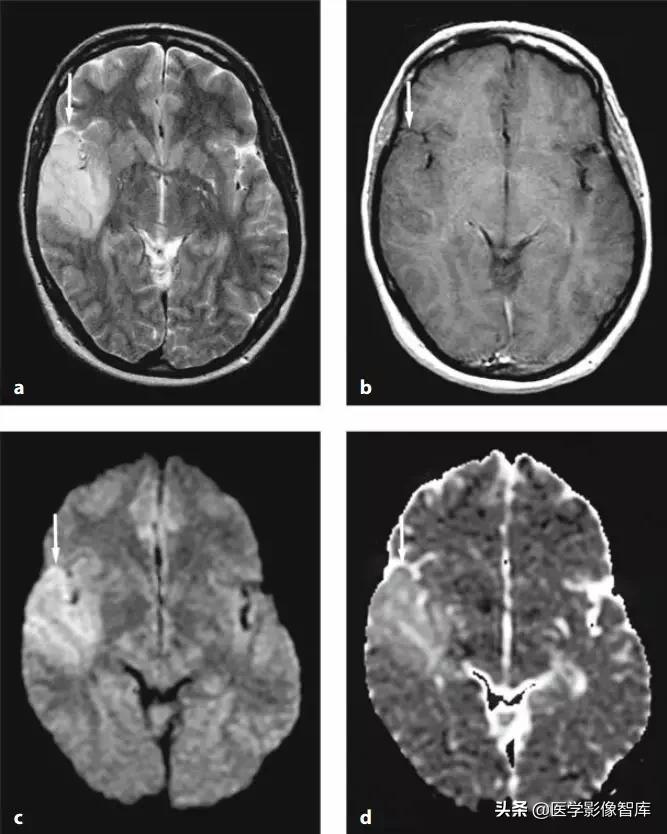

脑炎(包括病毒性脑炎、自身免疫性脑炎等)都有可能出现累及皮层 / 皮层下的 DWI 高信号。脑炎一般不难鉴别,急性起病,有发热、头痛等症状。累及皮层的脑炎会出现癫痫发作、精神症状等,行腰穿查脑脊液常规、生化、病毒抗体、自身免疫性脑炎抗体等可帮助诊断,图 1 为单疱脑炎患者发病 6 天时的磁共振检查结果。

图 1 单疱脑炎,起病 6 天,可见两侧颞叶病灶,右侧为甚,T2WI、FLAIR、DWI 均为高信号,ADC 图为低信号